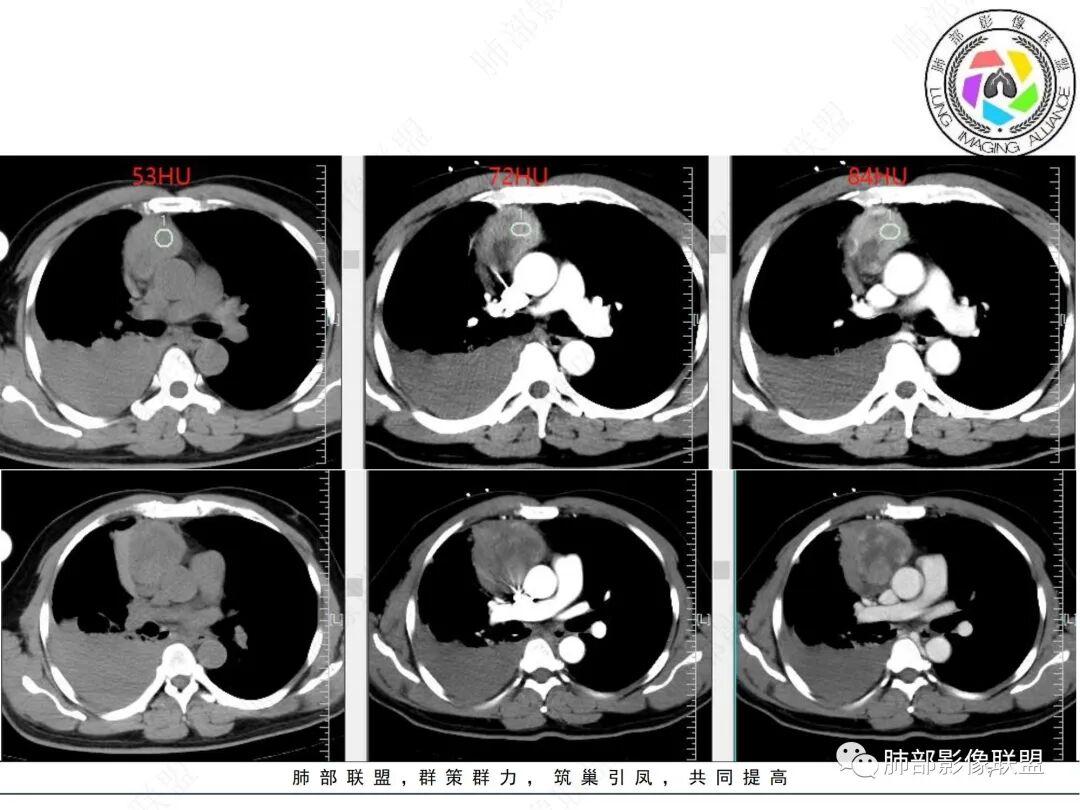

出血没问题:因为没强化

这是病灶,强化明显

这是出血

2、CT图像所见:前中纵隔肿块,偏于右侧生长,平扫及增强扫描见肿块形态欠规则,密度欠均匀,内部见低密度坏死区,实性部分及分隔可见轻中度渐进性强化,内部可见细丝状、短条状明显强化小血管影,肿块外侧见弧形高密度无强化影(其与纵隔肿块间脂肪间隙清晰),考虑为出血;右肺中上叶含气不良。右侧胸腔见高密度积液,从平扫到增强扫描短时间量明显增加,符合急性出血。肺窗见双肺胸膜下多发结节,右肺大片状磨玻璃影,左肺下叶磨玻璃结节。

3、综合分析:本例右前上纵隔肿块,内部坏死,实性部分中度渐进性强化,内部可见细丝状明显强化小血管影。肿块与周围血管分界尚清楚,周围脂肪间隙显示不清,邻近胸膜显示增厚,结合瘤体内出血,破入或渗入右侧胸腔,双肺胸膜下结节影,符合恶性肿瘤转移。

胸腺类癌影像特征:呈现纵隔偏侧性的生长,形态不规则,肿块体积通常较大,内见片状坏死区,增强扫描轻中度不均匀渐进性强化。肿瘤内部可见细丝状明显强化小血管影,推测此征象可能在胸腺类癌的诊断中有提示作用。肿瘤边界常不清晰,沿血管间隙侵袭性生长,易侵犯邻近纵隔大血管、心包、气管、食管等结构。钙化少见。